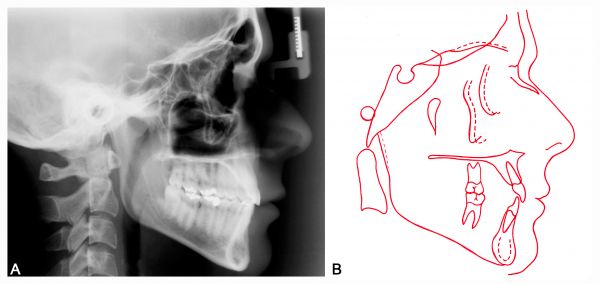

Telerradiografia e traçado inicial